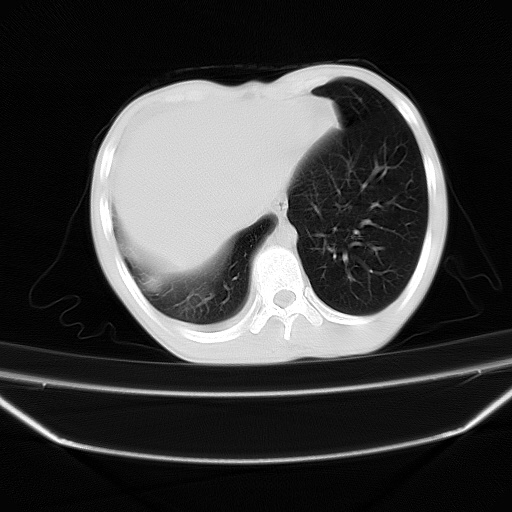

以下是引用zjzjr在2008-7-20 12:57:00的发言:[br]考虑为生殖源性肿瘤(内胚窦瘤),侵袭性胸腺瘤可能性大;右侧少量胸腔积液。

以下是引用xinliheng001在2008-7-20 21:17:00的发言:[br]右纵隔巨大分叶状软组织均质密度肿块,右上肺叶受压明显,纵隔右移、胸膜受累有少量积液和结节样增厚。应增强扫描一定会有更具诊断价值的信息。

以下是引用xinliheng001在2008-7-20 21:17:00的发言:[br]右纵隔巨大分叶状软组织均质密度肿块,右上肺叶受压明显,纵隔右移、胸膜受累有少量积液和结节样增厚。应增强扫描一定会有更具诊断价值的信息。